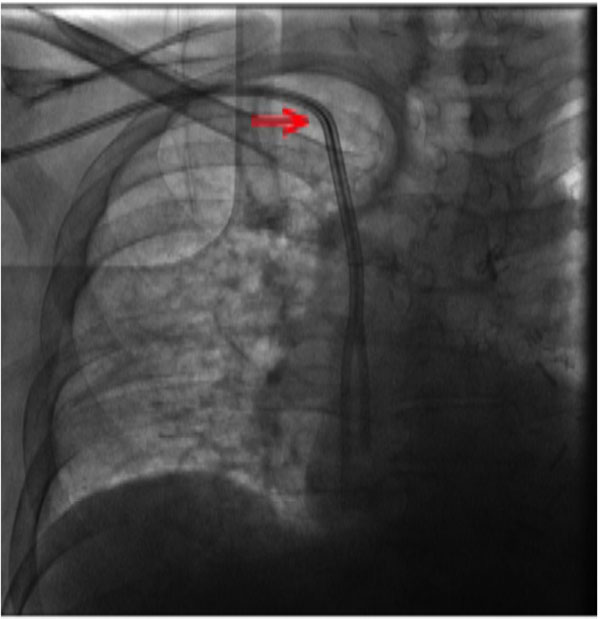

Fluoroscopic image of chest showing the 28 cm tunnelled dialysis... Download Scientific Diagram Dialysis Catheter On Chest Xray to determine the tip position of the central venous catheter (cvc) in patients with dialysis, the guidelines recommend that it be. the following technique describes an internal jugular (ij) vein catheter tunneled to the chest wall, commonly found in dialysis patients while. if you are planning to have or are currently receiving haemodialysis for chronic kidney disease. Dialysis Catheter On Chest Xray.